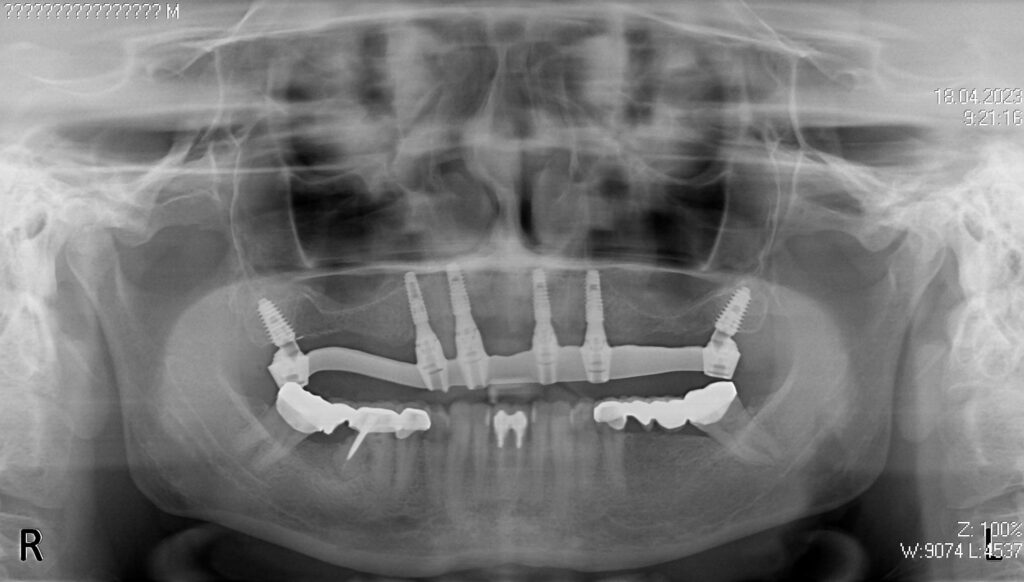

Лечение начато с выбора материала для будущей конструкции (диоксид циркония на титановой балке) и цвета.

Спустя 25 дней был зафиксирован протез с опопрой на дентальные имплантаты из диоксида циркония.

Установка 6-ти дентальных имплантантов Megagen Anyone

снимок